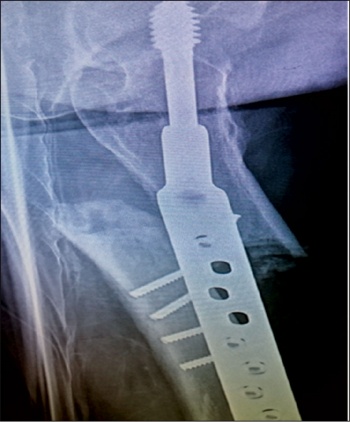

She was taken to theatre again and the DHS implant was removed. A long cephalomedullary nail was inserted. After that she was again started on physiotherapy.

The patient is being followed up in outpatients on a regular basis with check x-rays. She is now walking with a walking frame and is also on teriparatide injections.